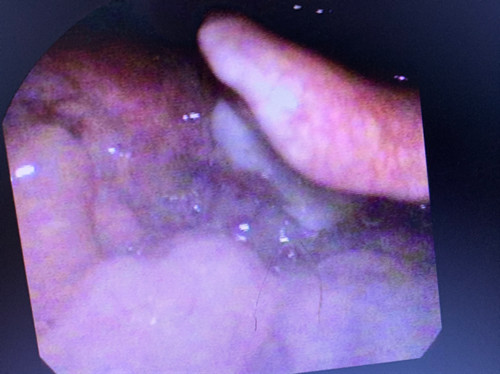

相关检查:间接喉镜、显微或电子喉镜检查,可发现位于会厌部位的类圆形或半球形肿物,表面光滑,蒂部广,可呈灰白、浅黄或淡红色。

低温等离子切除术后2周复查